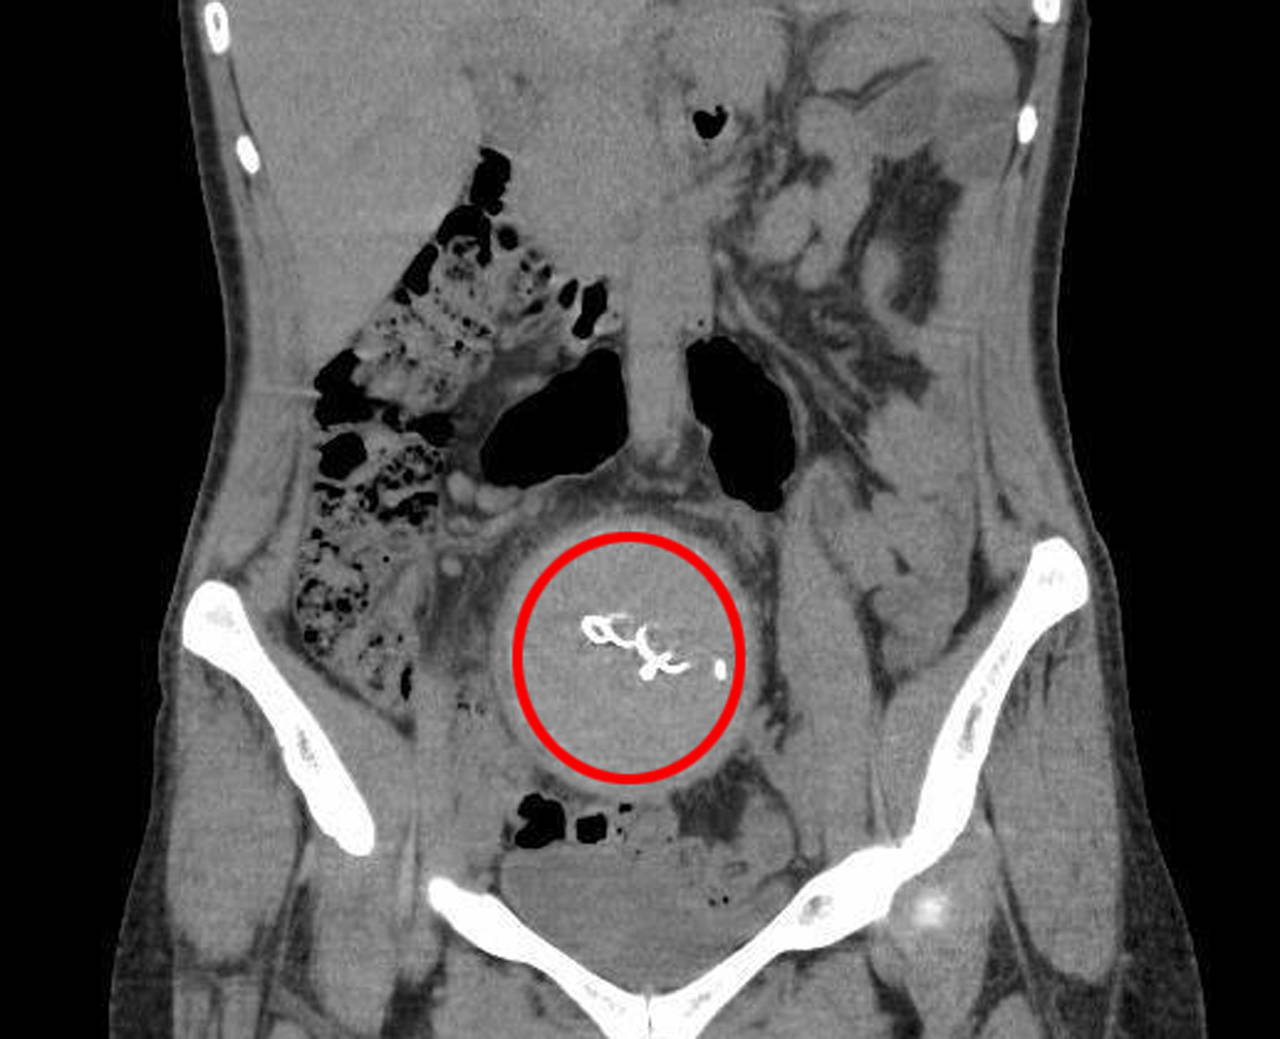

Burada yapılan kontrolde, doktor tomografi istedi. Çekilen tomografide, Y.S.'nin vücudunda doğum sonrası unutulan sargı bezi görüldü. İhmal nedeniyle 2 yıldır yaşadıklarından dolayı şoke olduğunu belirten Y.S.'nin vücudundaki 30 santimetrelik gazlı bez ameliyatla çıkarıldı.